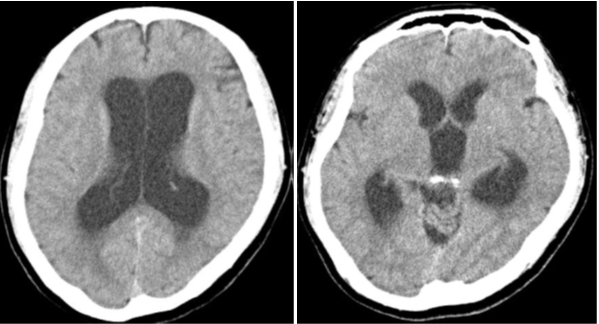

Figure 1 Noncontrast computed tomography showed a cyst in the pineal region with ventriculomegaly.

Figure 4 Postoperative computed tomography showed improvement in ventriculomegaly.